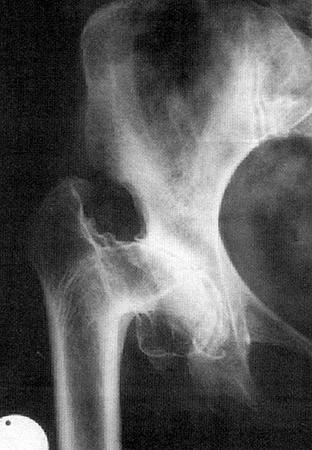

DIAGNÓSTICO Radiológico : – Pinzamiento de la interlínea articular – Esclerosis subcondral – Signo de Kiembock – Geodas – Osteofitos – Deformaciones en las superficies articulares

FASES DE LAS COXARTROSIS  Primera fase o incipiente Cambios en el aspecto del cartilago. Poco dolorosa, dsalvo en marchas prolongadas y permanencia de pie. Signos radiográficos y clinicos poco pronunciados.  Segunda fase o evolucionada. Destrucción del cartílago. Aparece rigidez y posiciones viciosas. El dolor aumenta y es persistente.  Tercera fase o final. Pérdida total del cartílago, osteofitos., signos óseos y capsulares más evidentes. Dolor muy intenso. Impotencia funcional muy marcada (posiciones viciosas persistentes)